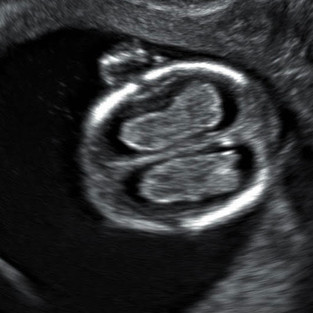

Esse exame deve ser realizado entre 11 semanas e 13 semanas e seis dias. Geralmente o exame é transvaginal, mas é complementado via abdominal. É um dos exames mais importantes da gestação. Toda mulher tem um risco de ter um bebê com Síndrome genética que geralmente é proporcional a sua idade. Isso é chamado de risco basal, ou seja, quanto mais velha maior o seu risco. Nesse exame, especialmente nessa idade gestacional, o bebê nos dá umas “pistas” que sinalizam que ele tem uma maior chance de ter síndromes.

Logo, esse exame não fecha o diagnóstico. Ele apenas nos dá uma probabilidade de o feto ser portador de cromossomopatias.

* Translucência nucal (acúmulo de liquido atrás do pescoço)

* Osso nasal

* Ducto venoso (um pequeno vaso próximo ao coração)

* Tricúspide

Fetos com translucência nucal aumentada de espessura, com ausência do osso nasal e com alteração dos fluxos no ducto venoso e na tricúspide, são incluídos em um grupo de alto risco. Esses casos têm indicação de realizar exames mais específicos para fazer o real diagnóstico da Síndrome, caso a mão deseje saber antes do parto.